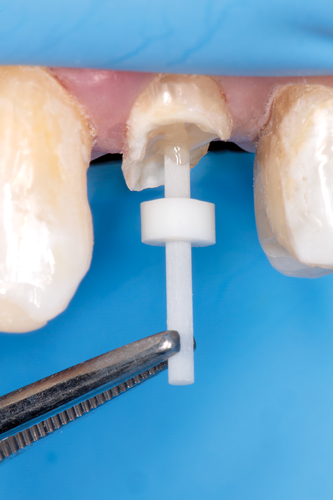

Fig 12. The preselected fiber-reinforced composite post was placed into the channel space, and the coronal height was measured and marked.

Figure 12

Fig 13. The channel preparation was etched for 15 seconds with 37.5% phosphoric acid semigel.

Figure 13